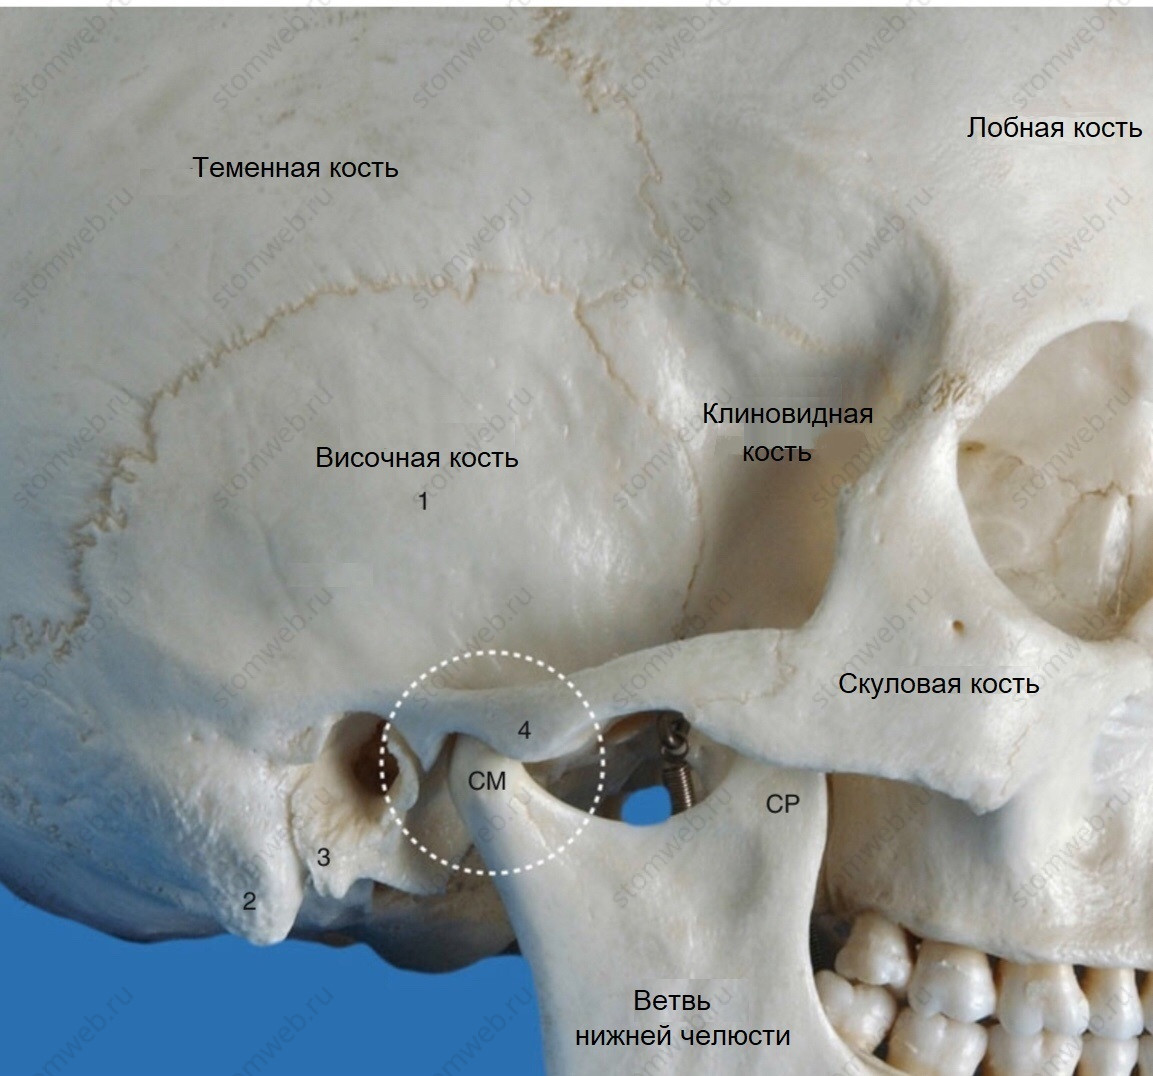

Анатомия сосцевидного отростка